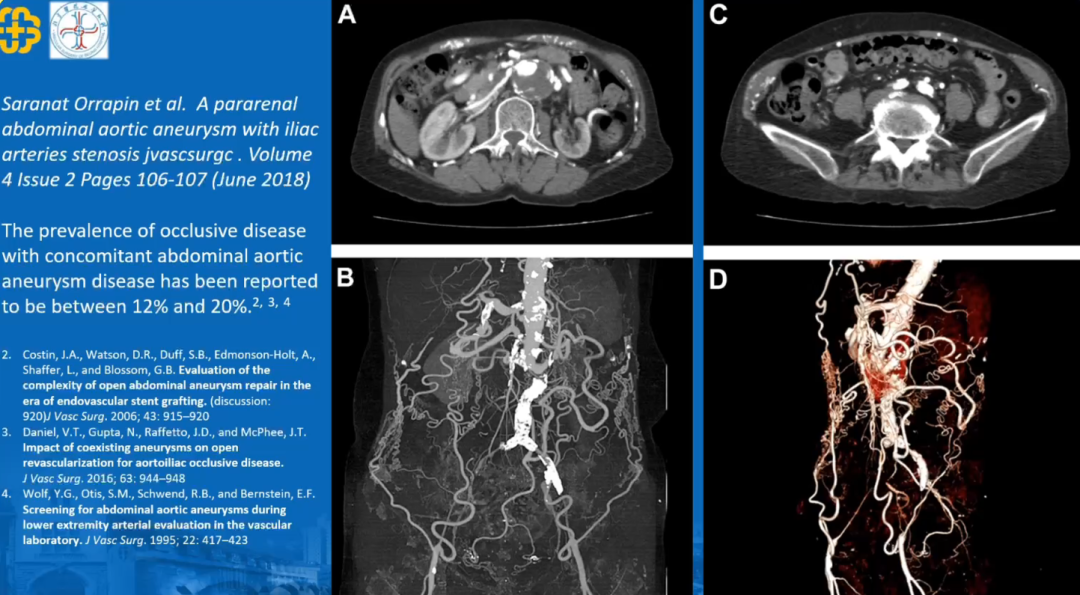

3. 合并动脉扩张性病变

文献中狭窄性病变或者闭塞性病变同期可以合并动脉扩张性病变,数据提示有20%主髂动脉病变患者同时合并有腹主动脉瘤或髂动脉瘤。因此,对于该病变的开通要注意病变的特点。

结合主髂动脉闭塞性病变的特点,不同病因、不同累及的范围、迂曲病变的钙化程度以及是否合并有扩张性病变,治疗选择当中都是需要考量的因素。